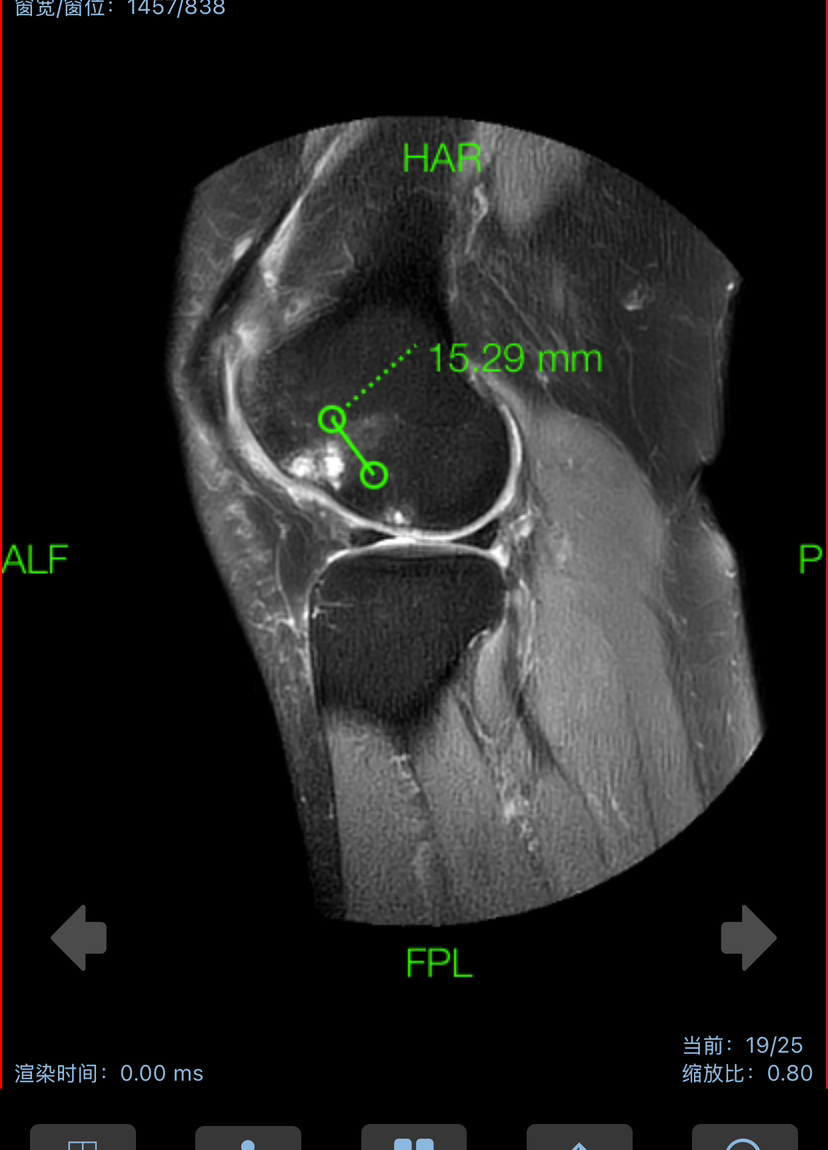

滑车软骨损伤 (软骨剥脱,软骨下骨暴露)

下面展示典型的膝关节软骨损伤,MRI核磁扫描可以清晰发现软骨损伤(3-4度),门诊检查非常常见!